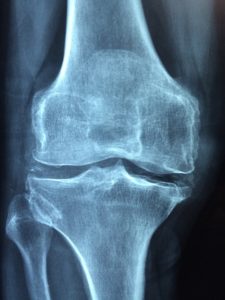

Ginger reduces inflammation similar to non-steroidal anti-inflammatory drugs (NSAIDs), such as aspirin and ibuprofen. Ginger contains COX-2 inhibitors, which suppress pain-causing enzymes in the body during inflammation.[1] A study by the University of Georgia showed ginger consumption could reduce muscle soreness by up to 25 percent for an entire day[2]. Consume ginger regularly to reduce arthritis pain and tendonitis.